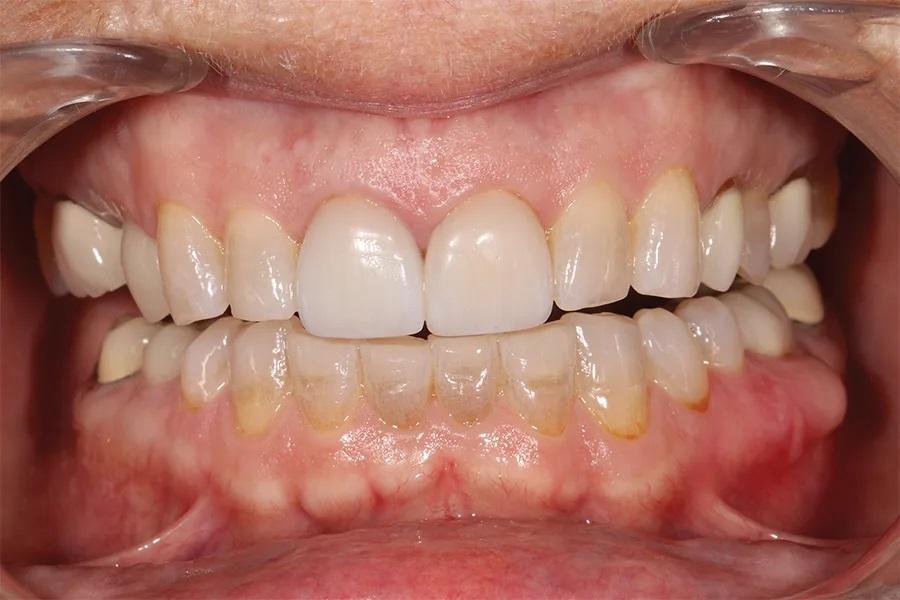

Фото 3. Вид с ретракторами до лечения. Отмечается генерализованный износ режущих краев и фасетки фрикционного износа на вестибулярной поверхности нижних резцов.

Пациентка, 58 лет, стоматолог-гигиенист, обратилась с жалобами на повторяющиеся неудачи реставрационного лечения. Она испытывала неудовлетворенность своим внешним видом (фото 1–3) и хотела получить более гармоничную, симметричную улыбку с более светлым оттенком зубов и меньшей выраженностью десневой улыбки. Будучи специалистом в области стоматологии, она понимала ограничения лечения отдельных зубов и, после многих лет разочарования, обратилась за комплексным долгосрочным решением, способным обеспечить стабильность, улучшить эстетику и предотвратить дальнейшее разрушение.